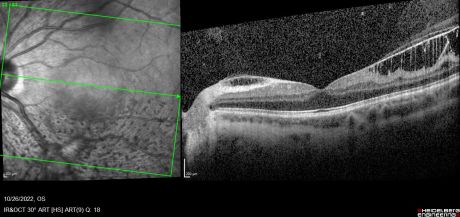

Combined cone and rod electroretinography (ERG) shows selective diminution of the b-wave (also known as a negative-ERG). Fluorescein angiography tends to show no abnormalities in the early phase of the angiogram but may show hyper-fluorescence and vascular leakage in late phases. [1] [3] Adaptive optics at 2- and 4-degrees eccentricity show normal cone cell count, photoreceptor packing geometry and intercellular spacing.[3] Optical coherence tomography of affected areas shows schisis retinal cavities mainly in the inner retinal layers but can extend to outer layers in later stages of the disease.[6]